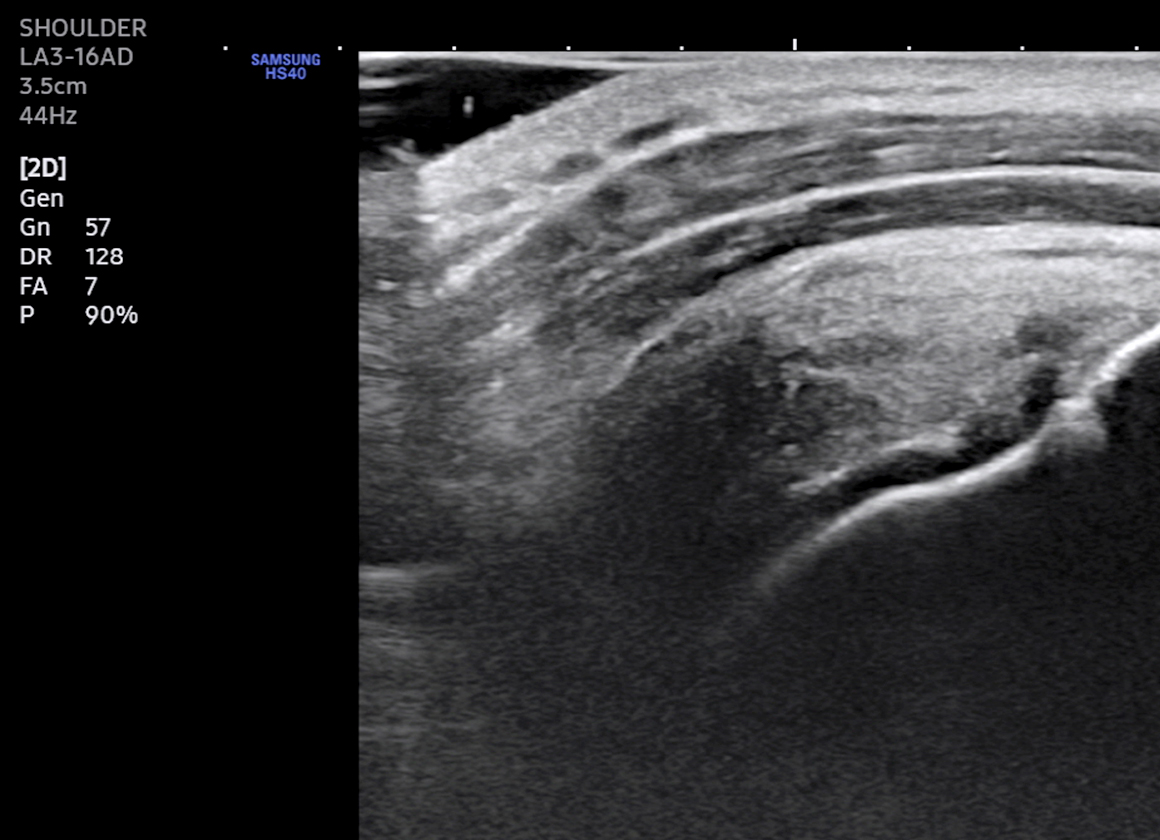

초음파 유도하 주사

치료 대상  :  관절염, 오십견, 건초염, 인대손상, 신경통증, 터널증후군, 근막염, 다한증 등

초음파 영상을 통해 병변의 진단과 함께 인대나 힘줄의 손상부위, 어깨나 무릎 등의 관절강 내 정확한 위치로 주사 치료를 시행합니다.